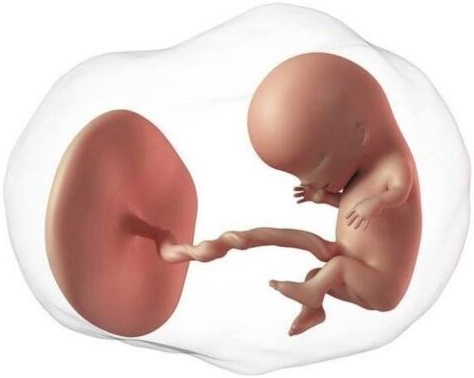

El embrión crece muy rápido, ha pasado de 4 a 14 mm en sólo una semana. Los cambios son impresionantes. En esta etapa inicia la formación de las neuronas y el cerebro ya tiene los dos hemisferios. En la cara aparecen las fosas nasales. El corazón ya tiene dos cámaras (al terminar su formación tendrá cuatro). Inicia la formación de los intestinos los cuales sobresalen a través del cordón umbilical que también está en proceso de formación.

Otro evento maravilloso es la formación de la placenta. La placenta se pone en contacto con el útero para obtener nutrientes y oxígeno. Aunque la placenta es un "órgano fetal", tiene la mitad de sus genes del padre. Para tu sistema de defensa es un tejido extraño, como un trasplante de otra persona. El sistema de defensa se regula para no rechazarla, pues las células de la placenta tienen "un permiso especial", diferente a cualquier otra célula humana, y además producen unas proteínas que se comunican con tus defensas. Con todo ello, el sistema inmunitario "reconoce" que se trata de la placenta y actúa de forma única en toda la biología: no sólo no ataca a un tejido extraño, sino que lo protege y se deja "invadir".